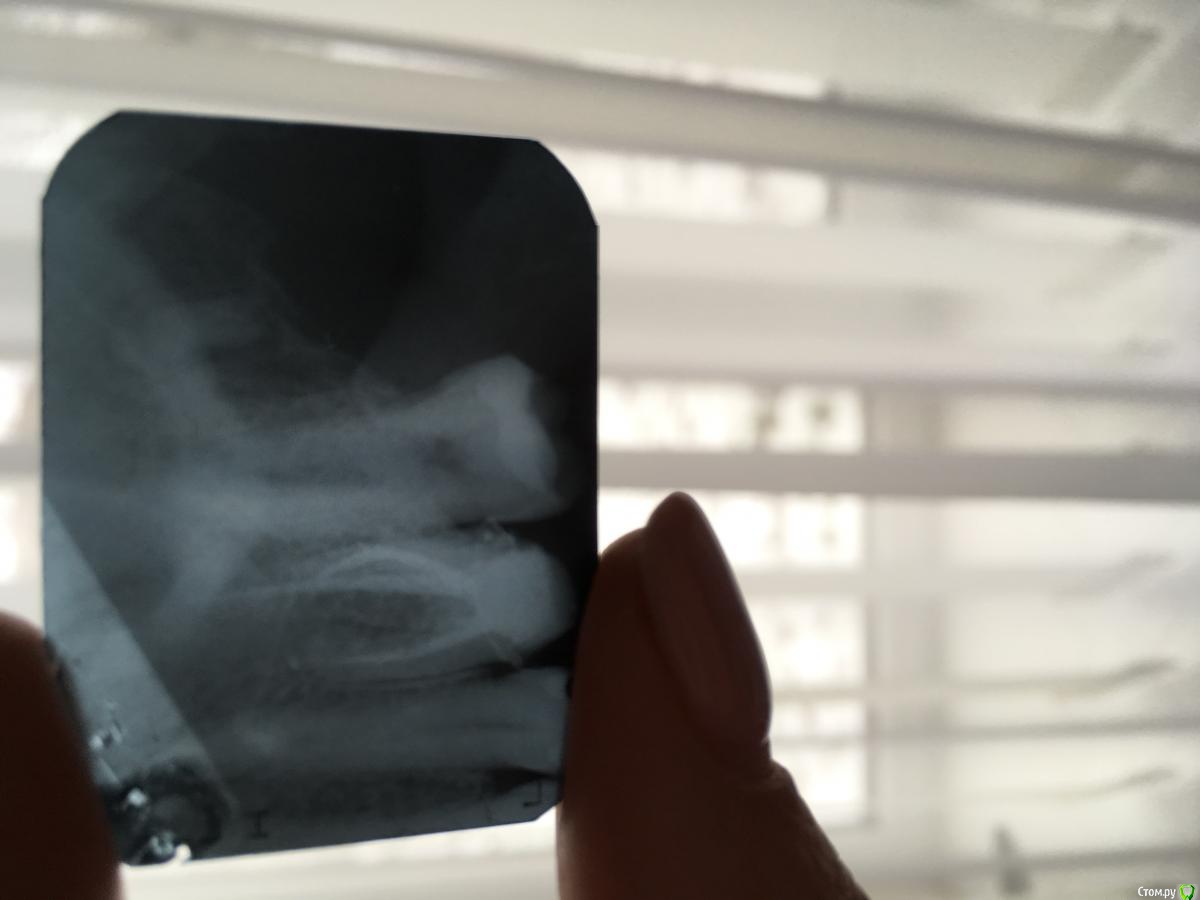

Evadiro Опубликовано 7 декабря, 2017 Поделиться Опубликовано 7 декабря, 2017 (изменено) 4 месяца назад удалили верхнюю 8.Все зажило без осложнений.Сегодня стало известно (на R снимке),что остался кусочек корня.Хирург посоветовал ничего не трогать пока не беспокоит. Правильно ли это? Изменено 7 декабря, 2017 пользователем Evadiro 1 Ссылка на комментарий

Evadiro Опубликовано 7 декабря, 2017 Автор Поделиться Опубликовано 7 декабря, 2017 Почему удаляли зуб?Сказали,что лечить нет смысла,так как к нему трудно подобраться.Сам зуб меня не беспокоил,был живой. Ссылка на комментарий

Marika Опубликовано 7 декабря, 2017 Поделиться Опубликовано 7 декабря, 2017 Пускай меня поправят,но я бы не трогала пока. Ссылка на комментарий

dok1 Опубликовано 9 декабря, 2017 Поделиться Опубликовано 9 декабря, 2017 Возможность удаления напрямую зависит от степени открывания рта. Но если не болит - забудьте. Ссылка на комментарий

___49___ Опубликовано 10 декабря, 2017 Поделиться Опубликовано 10 декабря, 2017 Не люблю остатки с деструктивными изменениями вокруг - убрал бы. Ссылка на комментарий